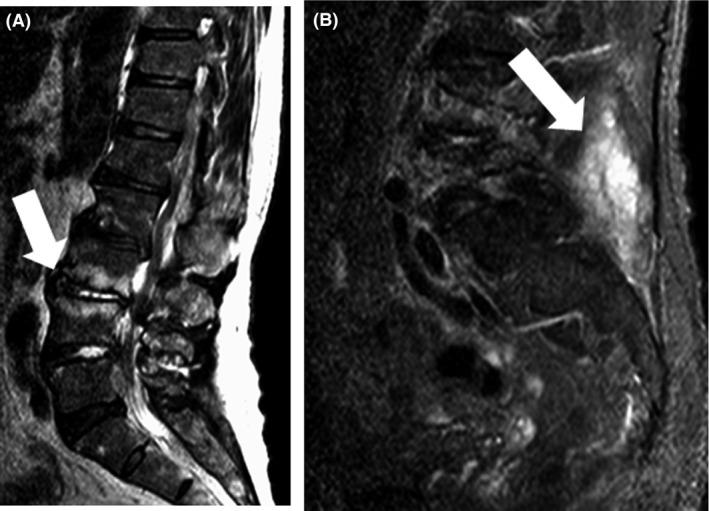

In rare cases, spinal epidural abscess involves the entire spine and can lead to neurological deficits and sepsis if treatment is delayed or suboptimal. A 65-year-old man was admitted with a diagnosis of bacterial meningitis. After admission, magnetic resonance imaging showed a spinal epidural abscess from the cervical to lumbar spine. Blood culture revealed . The patient was initially treated medically because he had no neurological deficits. Repeat blood culture remained positive and abscesses were found in the mediastinum and bilateral psoas muscles.

在罕见情况下,脊柱硬膜外脓肿可累及整个脊柱,如果治疗延迟或不充分,可导致神经功能缺损和脓毒症。一名65岁男性因细菌性脑膜炎入院。入院后,磁共振成像显示从颈椎至腰椎存在脊柱硬膜外脓肿。血培养显示……患者最初接受药物治疗,因为他没有神经功能缺损。重复血培养仍为阳性,且在纵隔和双侧腰大肌发现脓肿。